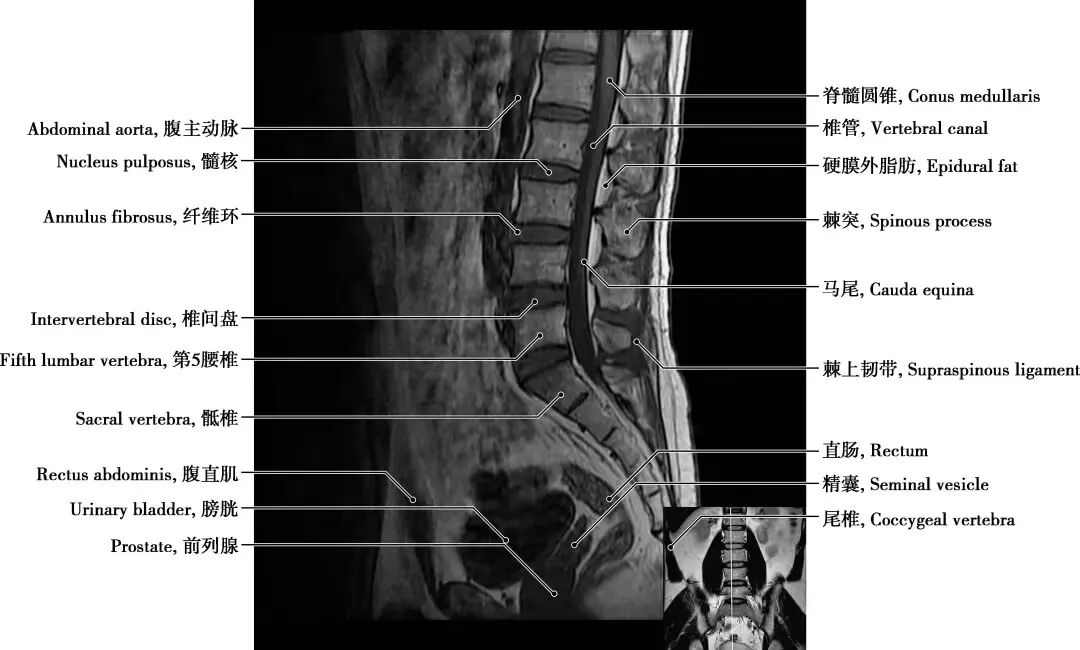

三、核磁共振(MRI):这是一种利用强磁场和射频信号的高级检查方法。

优点:磁共振检查在软组织成像上更胜于腰椎CT。可以很好地观察腰椎间盘的情况,更清晰地显示椎间盘的形态及其与硬膜囊、神经根等周围组织的关系。在脊髓病变、炎性病变、出血性病变及腰部肌肉病变等方面也具有优势。此外,磁共振检查不存在X线辐射,是较为安全可靠的检查。

缺点:价格较高,时间较长,有明确的限制人群,如有金属植入物、胰岛素泵或者心脏起搏器的患者。此外,因磁共振机器的孔径一般都不是很大,所以患有幽闭恐惧症的患者,也不建议首选腰椎MRI。

最后,简单总结下,如果您只是轻微的腰痛,没有神经根受压的迹象(如下肢放射痛、麻木等),可以先做X线检查;如果有外伤或是评估骨质结构或是否有钙化,建议做CT检查;如果有神经根受压、软组织损伤或者怀疑肿瘤等严重情况,建议做MRI检查。